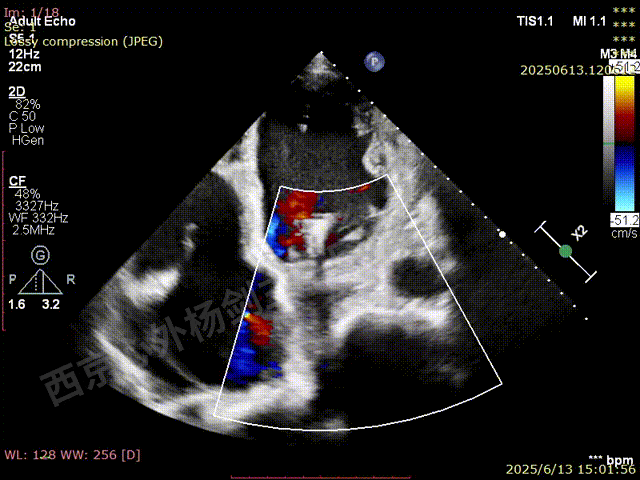

二尖瓣后叶栓系严重,前叶相对错位,反流束沿2区分布广泛,2偏3区处存在反流。

反流宽度至少23mm,因影像调整困难,考虑实际反流更宽。